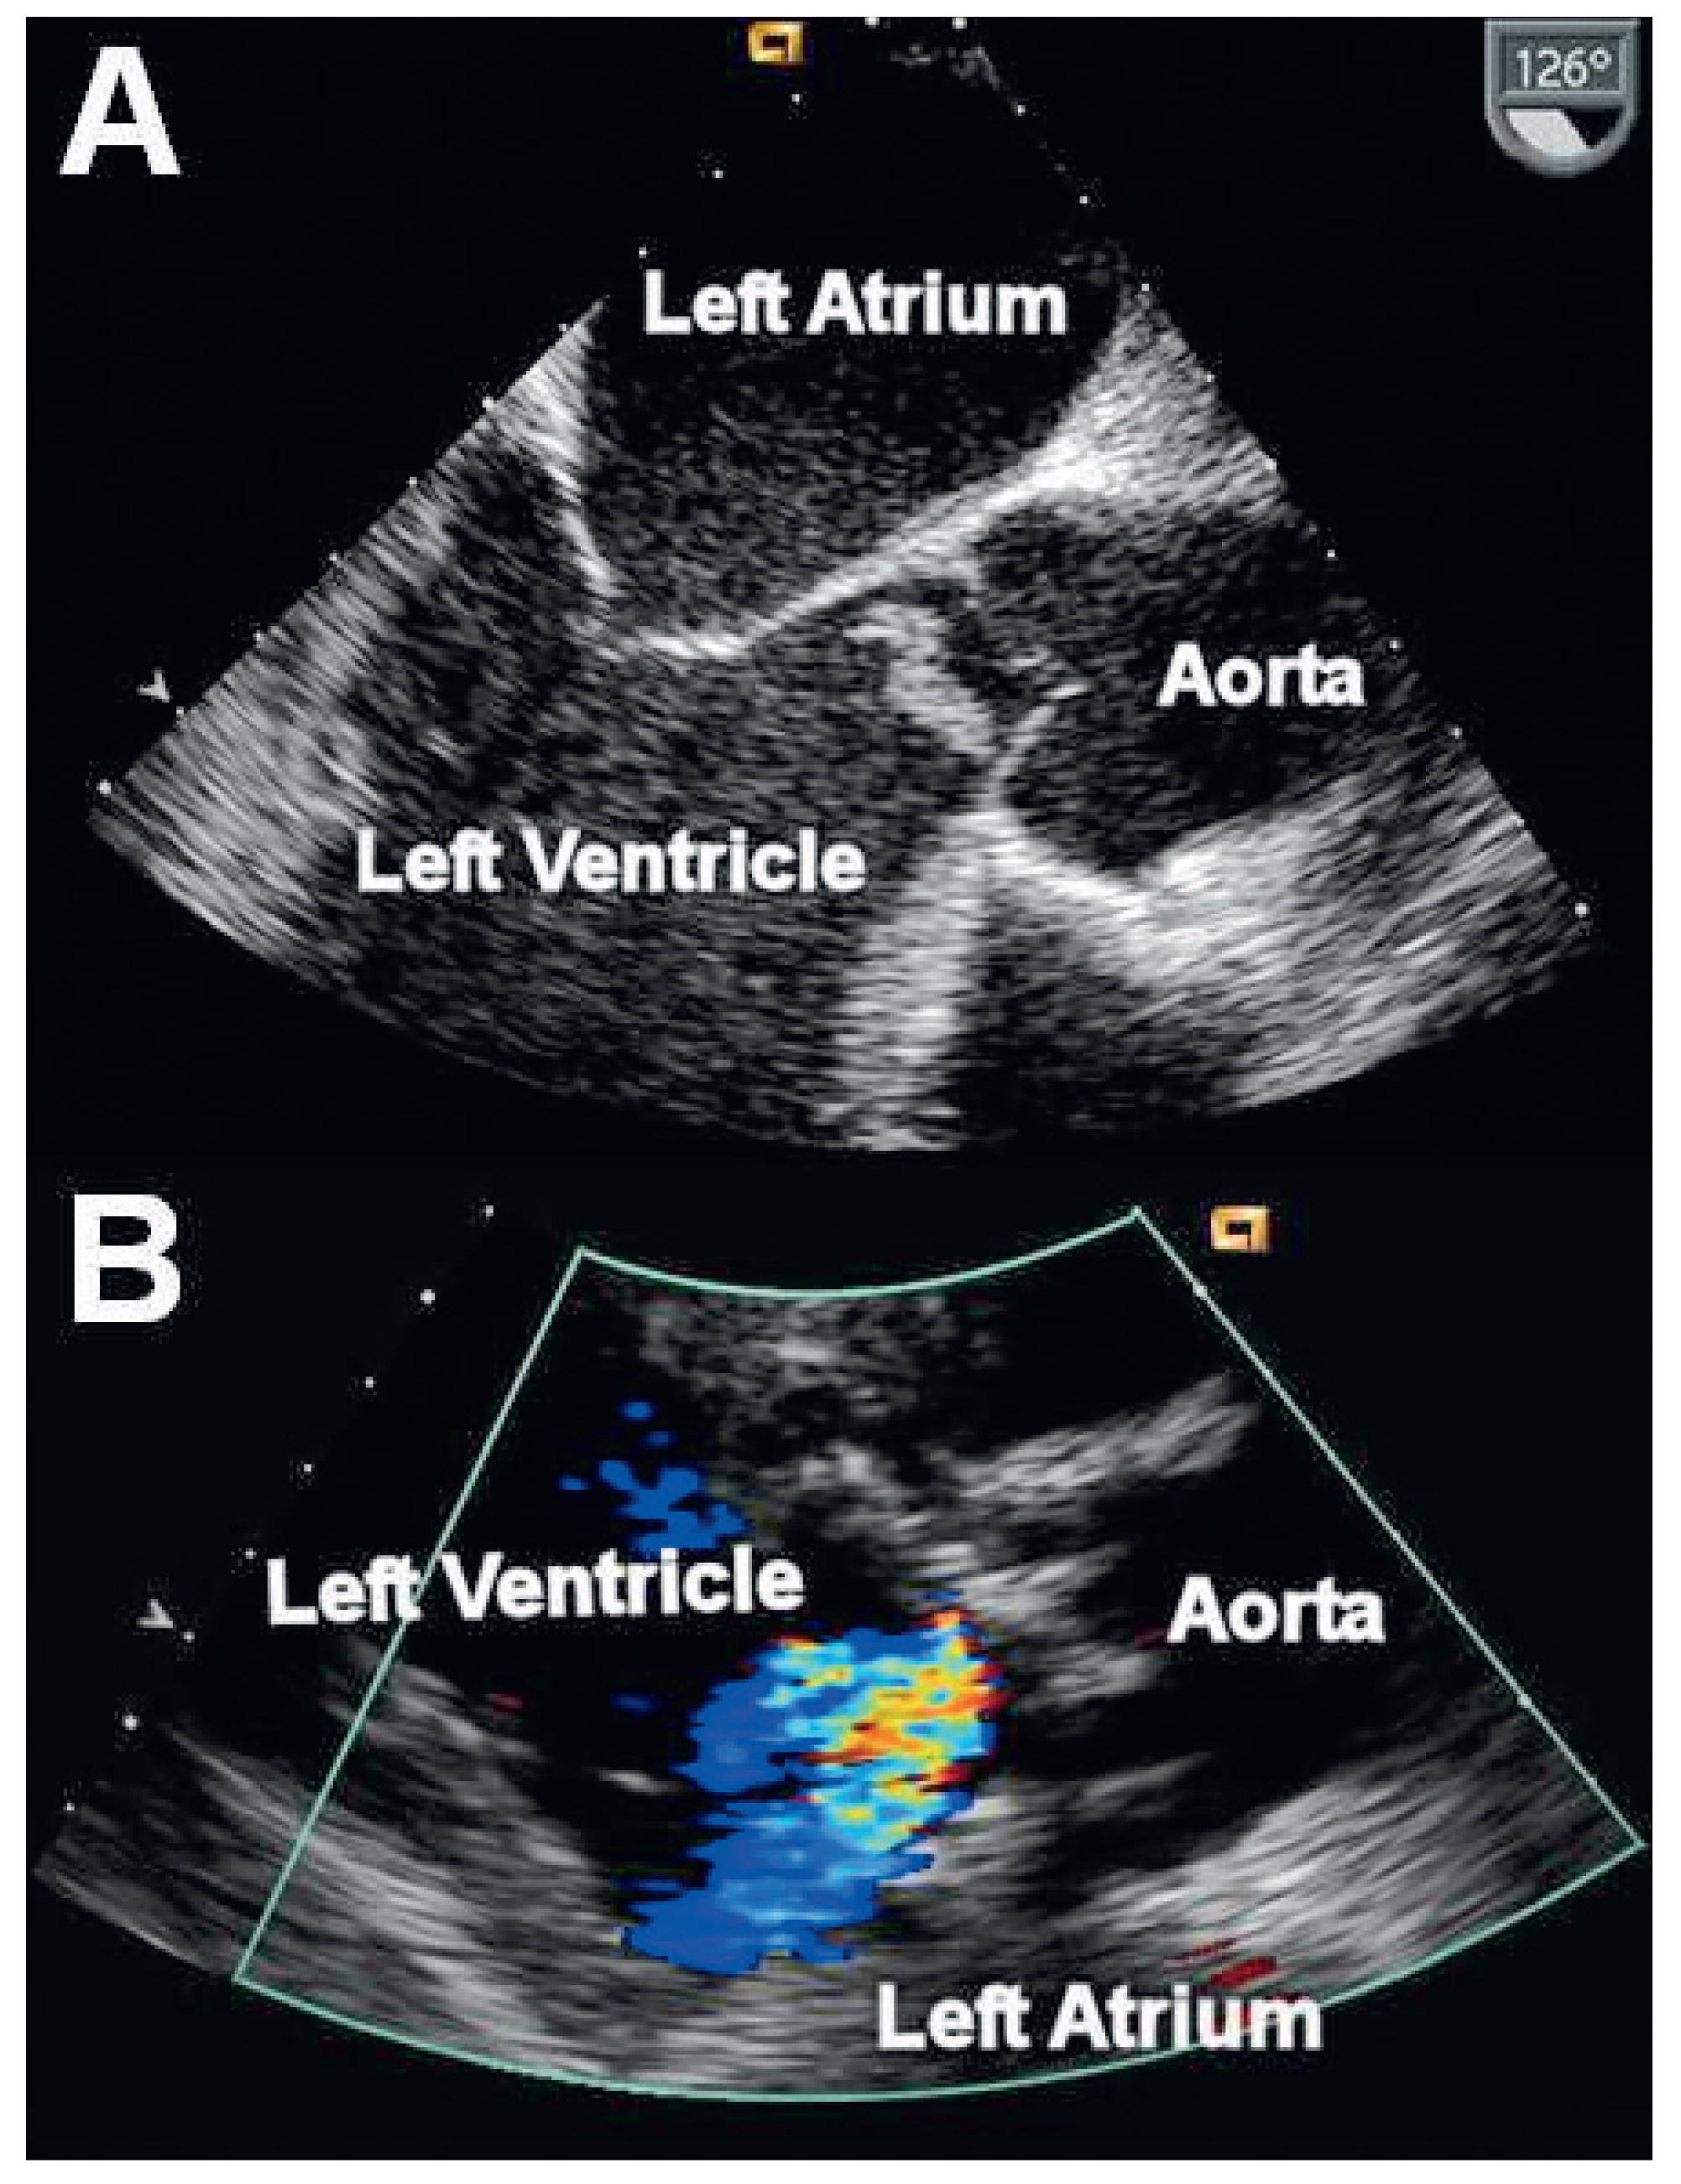

Morbus Behçet Associated Aortitis Mimicking Infective Endocarditis

Case report